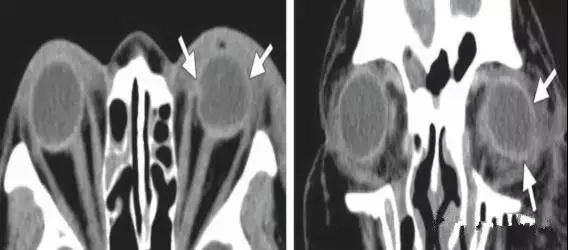

3.常见的用于治疗视网膜脱离的材料包括巩膜条带 , 硅油 , 以及气体 。

文章插图